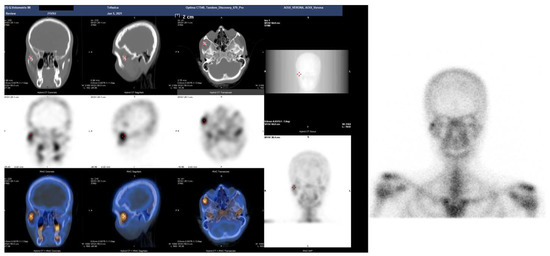

Figure 3.

SPET-CT showing bone reworking in correspondence to the joint between the jaw and the right zygomatic bone compared to the contralateral homologous site.